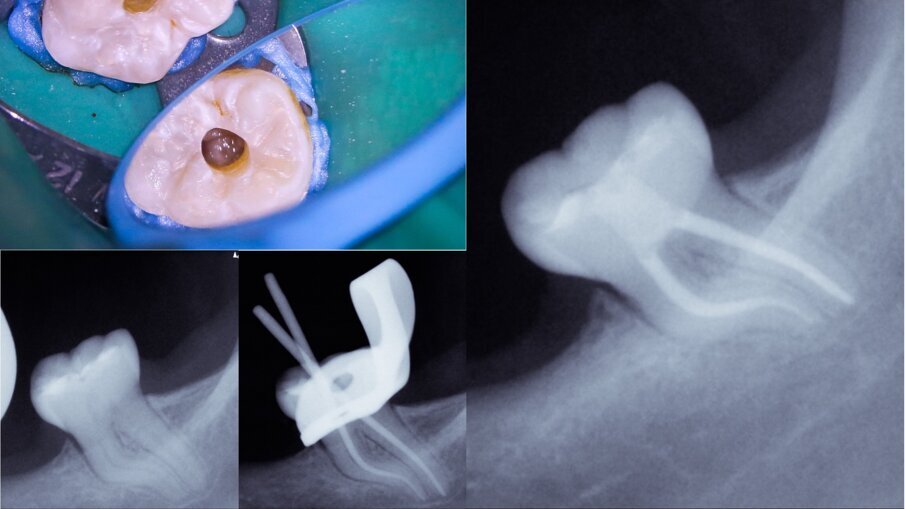

Figs. 4a–d: Root canal therapy performed through a conservative access cavity in a tooth #37 with severe curvatures at the mesial root. The root canal obturation was performed by the hydraulic compaction technique.

Figs. 5a & b: Root canal therapy performed in tooth #46 through a zirconia crown. The access cavity was prepared as conservatively as possible. The root canal obturation was performed by the hydraulic compaction technique.

One of the most challenging situations when working through conservative openings is the root canal obturation step. The lack of straight line access, compromised visibility and a reduced opening to properly clean the pulp chamber are factors to take into consideration.15 The physical properties of calcium silicate-based endodontic sealers allow clinicians to overcome those challenging aspects. The relatively easy obturation technique, flowability and easy process of cleaning the pulp chamber provide the necessary means for proceeding with the endodontic therapy as conservatively as possible without compromising the prognosis. In the clinical cases presented, the Aurum Blue system (Meta Biomed) was used for the root canal shaping and the calcium silicate-based endodontic sealer CeraSeal (Meta Biomed) was used, applied with the cold hydraulic compaction technique (see video below).